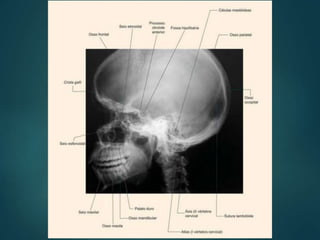

2- Processo ClinóideAnterior 3- Arco zigomático 4- Tubérculo para ATM 8- Clivo 9- Condilo da mandíbula 10-Sutura coronal 11- Processo coronóide da mandíbula 12-Diploe 13-Dorso da sela 14-Células Aéreas etmoidais 15-Meato Acústico Externo 16- Processo frontal zigomático 17-Seio Frontal 18- Asa menor do Esfenoide 19-Sulcos p/ vasos meníngeos 20-Sutura Lambdóide 21- Processo Zigomático da Maxila 22-Células Aéreas mastóideas 25- Processo palatino da maxila 26- Sela Turca 28- Processo clinóide Posterior 29- Ramo da Mandíbula 30- Seio Esfenoidal